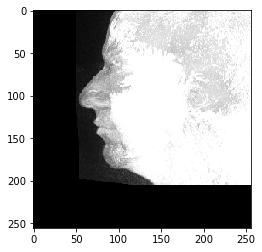

# 加载示例数据

np_array = imread('../../data/Haase_MRT_tfl3d1.tif')

np_array.shape

(192, 256, 256)

# 将其推送到GPU内存

input_image = cle.push_zyx(np_array)

cle.imshow(input_image)